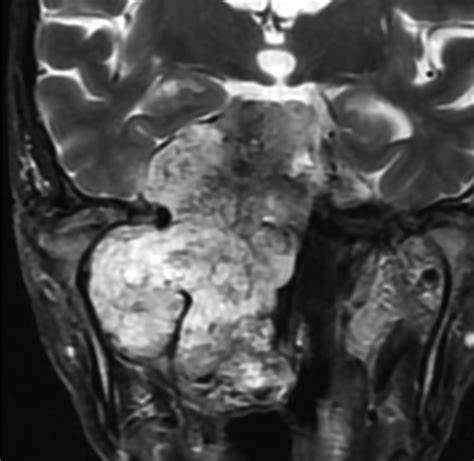

脊索瘤是一种呈黄色半透明红褐色的肿瘤,同时伴有钙化、出血、坏死、囊肿等症状。